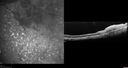

FUNDUS PHOTOGRAPHY - AUTO FLUORESCENCE: The image in the right eye shows white hyper auto fluorescence centrally where the white reflective lesion is. In the left eye those little leopard spots are hyper auto fluorescencent.